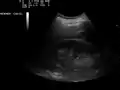

Ultrasound of liver (left side of the image) and right kidney (right side of the image) and Morison's pouch, not containing fluid